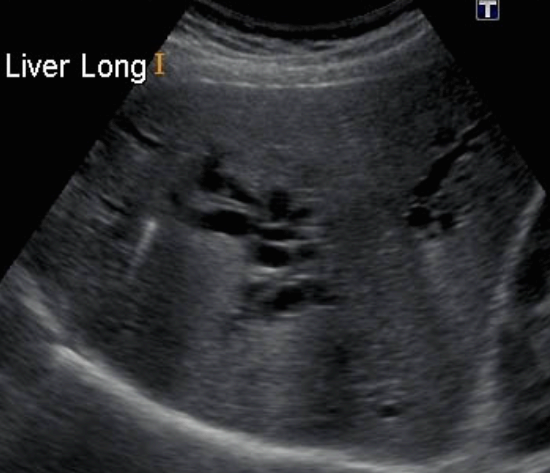

US finding

- 담관 내 무에코의 낭종

- 경계가 분명한 후방음향 증강

- 지방식 검사 후 수축소견이 없다.